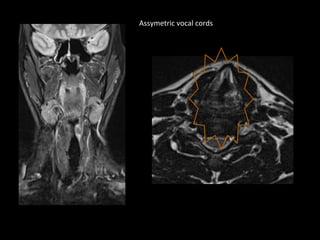

• Left vocal cord palsy.

Thickening of aryepiglottic fold on left side.

Assymetric vocal cords

So , is there a mass in larynx..?

• Direct laryngoscopy – no mass.

• Remember that chages seen in MRI are

secondary to recurrent laryngeal palsy.

• They do not represent tumor.

• Larynx imaging findings should always be

correlated with laryngoscopy findings